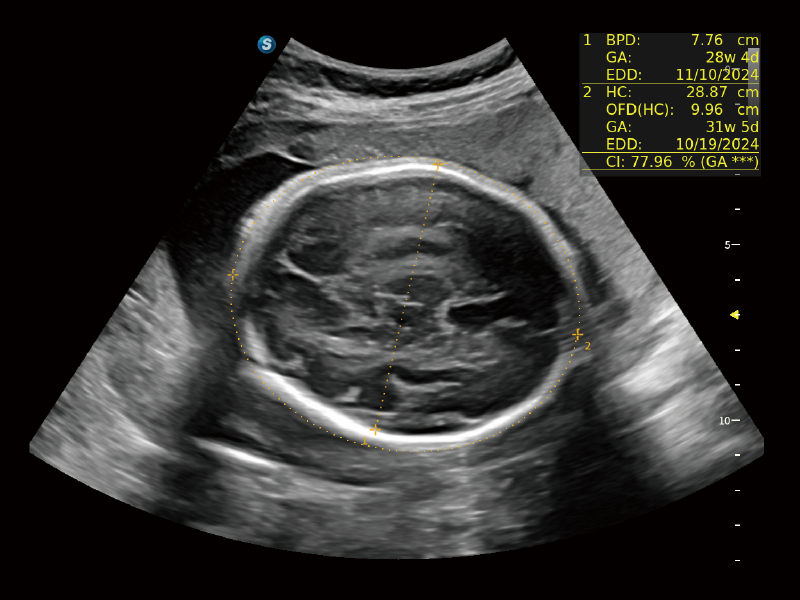

作為開(kāi)立醫(yī)療全新打造的超高端旗艦超聲產(chǎn)品,從探頭抬起喚醒開(kāi)啟掃查到多維探頭發(fā)射接收,通過(guò)先進(jìn)的場(chǎng)成像發(fā)射、自適應(yīng)聚合重建等技術(shù),基于RF Data原始射頻數(shù)據(jù)在圖像生成、高端功能等方面實(shí)現(xiàn)突破,為婦產(chǎn)科、兒科提供全方位臨床解決方案。

夢(mèng)溪?P80以“關(guān)愛(ài)女性”為基石,提供全方位的解決方案,量身定制以滿(mǎn)足女性的健康需求,涵蓋婦科、生殖健康檢查、產(chǎn)前篩查及產(chǎn)后康復(fù)等領(lǐng)域。